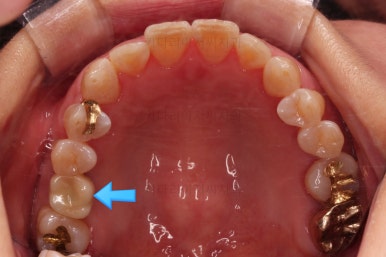

초진 때의 사진입니다.

임플란트를 위해서 쓰러진 어금니를 원위치 시키는 부분교정을 시행한 뒤, 해당 부분에 임플란트를 하기로 했답니다.

점점 자리가 확보되어가는게 보이시죠?

교정치료와 임플란트를 병행하면서 치아 빠진 부위가 다행히 잘 마무리가 되었네요.

쓰러진 치아도 원위치로 만들어 기능을 회복시켜주었고, 임플란트도 1개로 마무리를 할 수 있었어요.